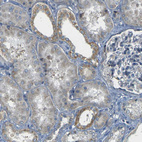

Immunohistochemical staining of human kidney shows weak to moderate cytoplasmic positivity in cells in tubules.